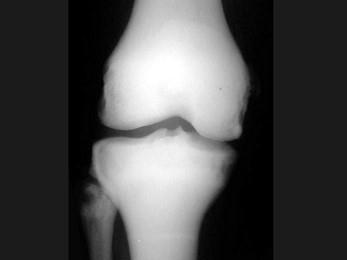

男,23岁,根据影像图像,最可能的诊断是?(?)A.骨髓炎B.骨硬化症C.骨囊肿D.骨脓肿E.骨结核

问题 男,23岁,根据影像图像,最可能的诊断是?(?)

选项 A.骨髓炎 B.骨硬化症 C.骨囊肿 D.骨脓肿 E.骨结核

答案 B